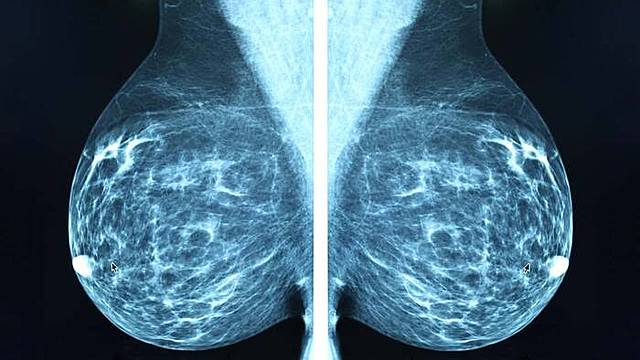

• La primera mamografia digital

La primera mamografia digital

Se dispone del primer sistema de imagen de mamografia digital directo.